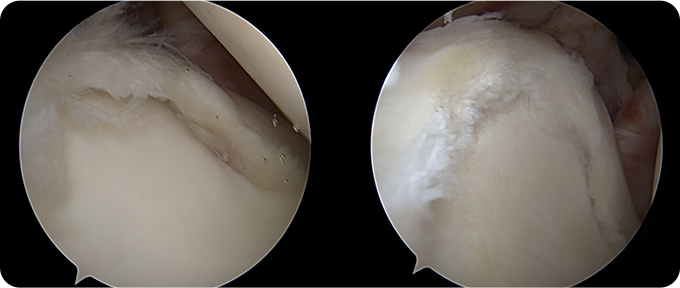

연골 봉합술&절제술

손상된 십자인대를 제거하고 새로운 인대를 이식하여 무릎 관절의 안정성을 회복하는 수술입니다. 이 수술은 관절내시경을 통해 진행되며, 최소 절개로 합병증 위험을 줄이고 회복 속도를 높이는 장점이 있습니다. 수술 후에는 체계적인 재활 프로그램을 통해 관절 가동 범위를 회복하고 근력을 강화하며, 일상생활로의 복귀를 목표로 합니다.